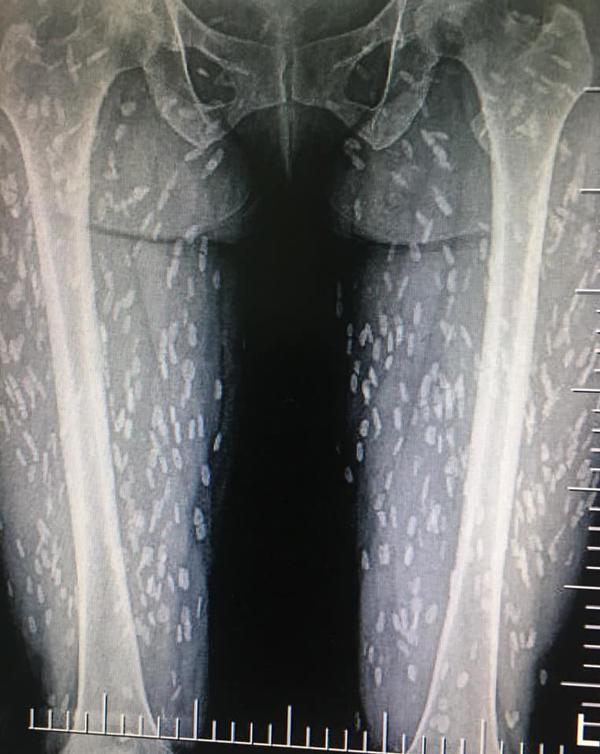

Gần đây một cư dân mạng Thái Lan đã gây xôn xao bằng 2 bức ảnh chụp X-quang khiến bất cứ ai cũng phải giật mình kinh hãi.

Theo như bài viết chia sẻ thì một người phụ nữ thường ăn thịt lợn tái, chưa chín khiến cơ thể cô bị xâm chiếm bởi hàng trăm ký sinh trùng. Trước đó, người phụ nữ cảm thấy cơ thể đột nhiên mệt mỏi bất thường và khó thở nên đã tới bệnh viện khám.

Sau khi chụp X-quang, thấy khắp cơ thể đặc biệt đầy những đốm trắng lạ kỳ. Bác sĩ khi nhìn vào cũng vô cùng kinh ngạc và cho biết đây là những ký sinh trùng đang nằm trên khắp cơ thể nữ bệnh nhân, đặc biệt là phần chân.

Bác sĩ cũng cảnh báo nếu toàn bộ ký sinh trùng này không được loại bỏ thì chỉ một thời gian ngắn nữa, nó có thể gây suy hô hấp hoặc thậm chí tử vong.

Loại ký sinh trùng này được xác định là ấu trùng của sán dải heo hay sán dải lợn. Những nang ấu trùng nhiễm vào não, cơ hoặc các mô khác có thể gây ra các cơn động kinh khởi phát tuổi trưởng thành.